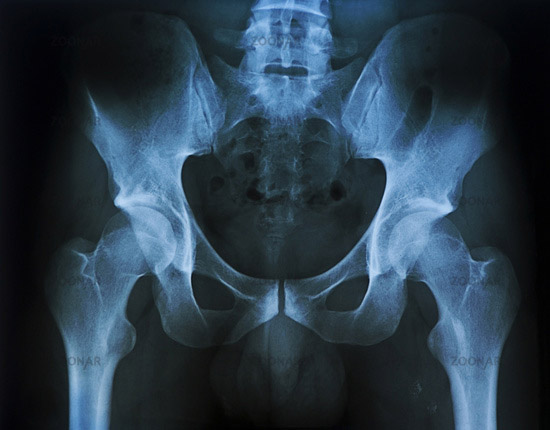

Neden leğen kemiği kayar?

Femur kemiğinin origosunun baş kısmı kendi yuvasından aşağıya ya da yukarı doğru kayıyor.Bu kayma sonucunda pelvis kemiğinin yanaklarından biri kayma sonucunda eğim kazanıyor.Eğim gerçekleştiğinde sacrumdan başlayıp lumbal bölgeyi ve sonrasında tüm vertebra disklerini kendi eksenlerinde döndürüyor.

Disklerin içi sıvı kıvamında ve dışa doğru koyulaşıp kabuklaşan bir yapıdadır,bu sayede kolay şekil değiştirebilir. Yukarıdan aşağıya bastırılan yüklerin bir tarafa eğik basması halinde bile bu yumuşaklık sayesinde bir alta yükü eşit dağıtır.Ani ve ters yüklenmeler sonucunda vertebra diskleri intervertebral disk kıkırdağının (pulpeus) etrafında sağ sola hareket edebiliyor.Bir disk döndüğünde nerelere zarar veriyor bunu bir disk kaydığında neler olur butonuna tıklayarak öğrenebilirsiniz